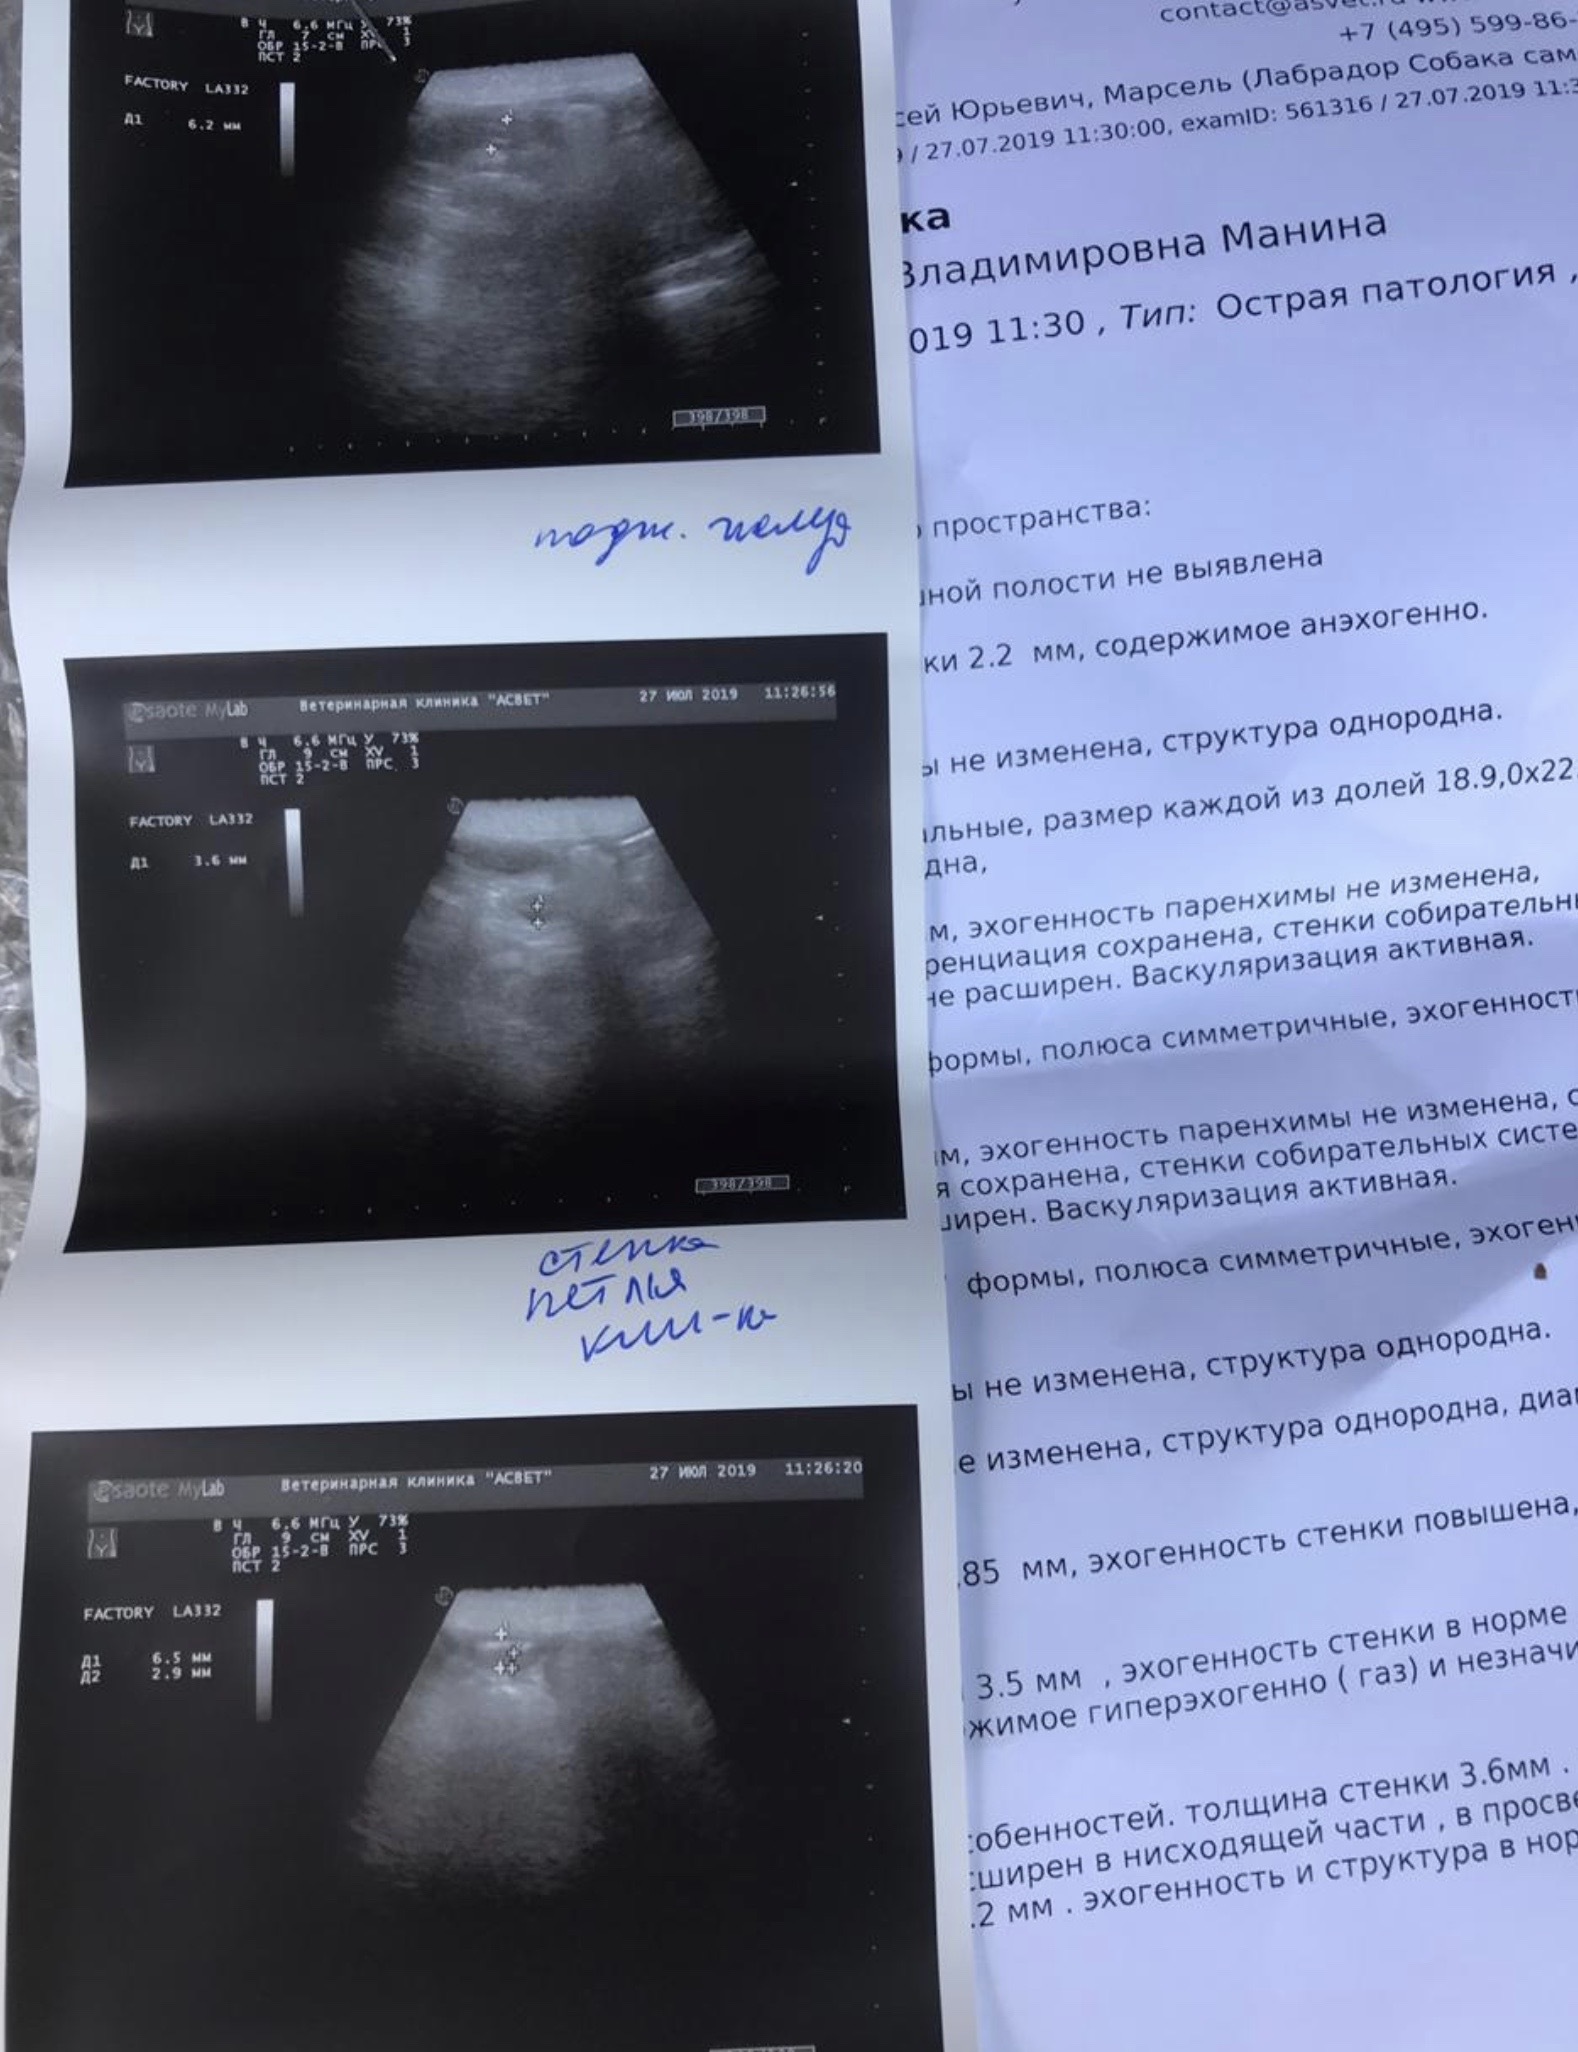

Mosfilmka & Remy Опубликовано 27 июля, 2019 Автор Опубликовано 27 июля, 2019 Масяня съездил в клинику и прошел исследования. Правда, посчитал, что его на процедурах собираются убивать, поэтому усиленно звал на помощь Алексеева наказала сдать анализ на кровепаразитов ибо в тех местах, где он жил, запросто можно подхватить. Остаток на 26.07 5350руб Приход: 0 Расход: 5935руб - обследование 195руб - глазные капли 3000руб - передержка с 22.07 по 31.07 Итого расход: 9130руб. ИТОГО: МИНУС 3780руб.

Mosfilmka & Remy Опубликовано 29 июля, 2019 Автор Опубликовано 29 июля, 2019 Результаты анализов. Пришли все отрицательные на кровепаразитов, что не может не радовать! Елена Анатольевна наказала повторить анализ через 10-14дн, а также снова сдать клинику, назначила гемобаланс.